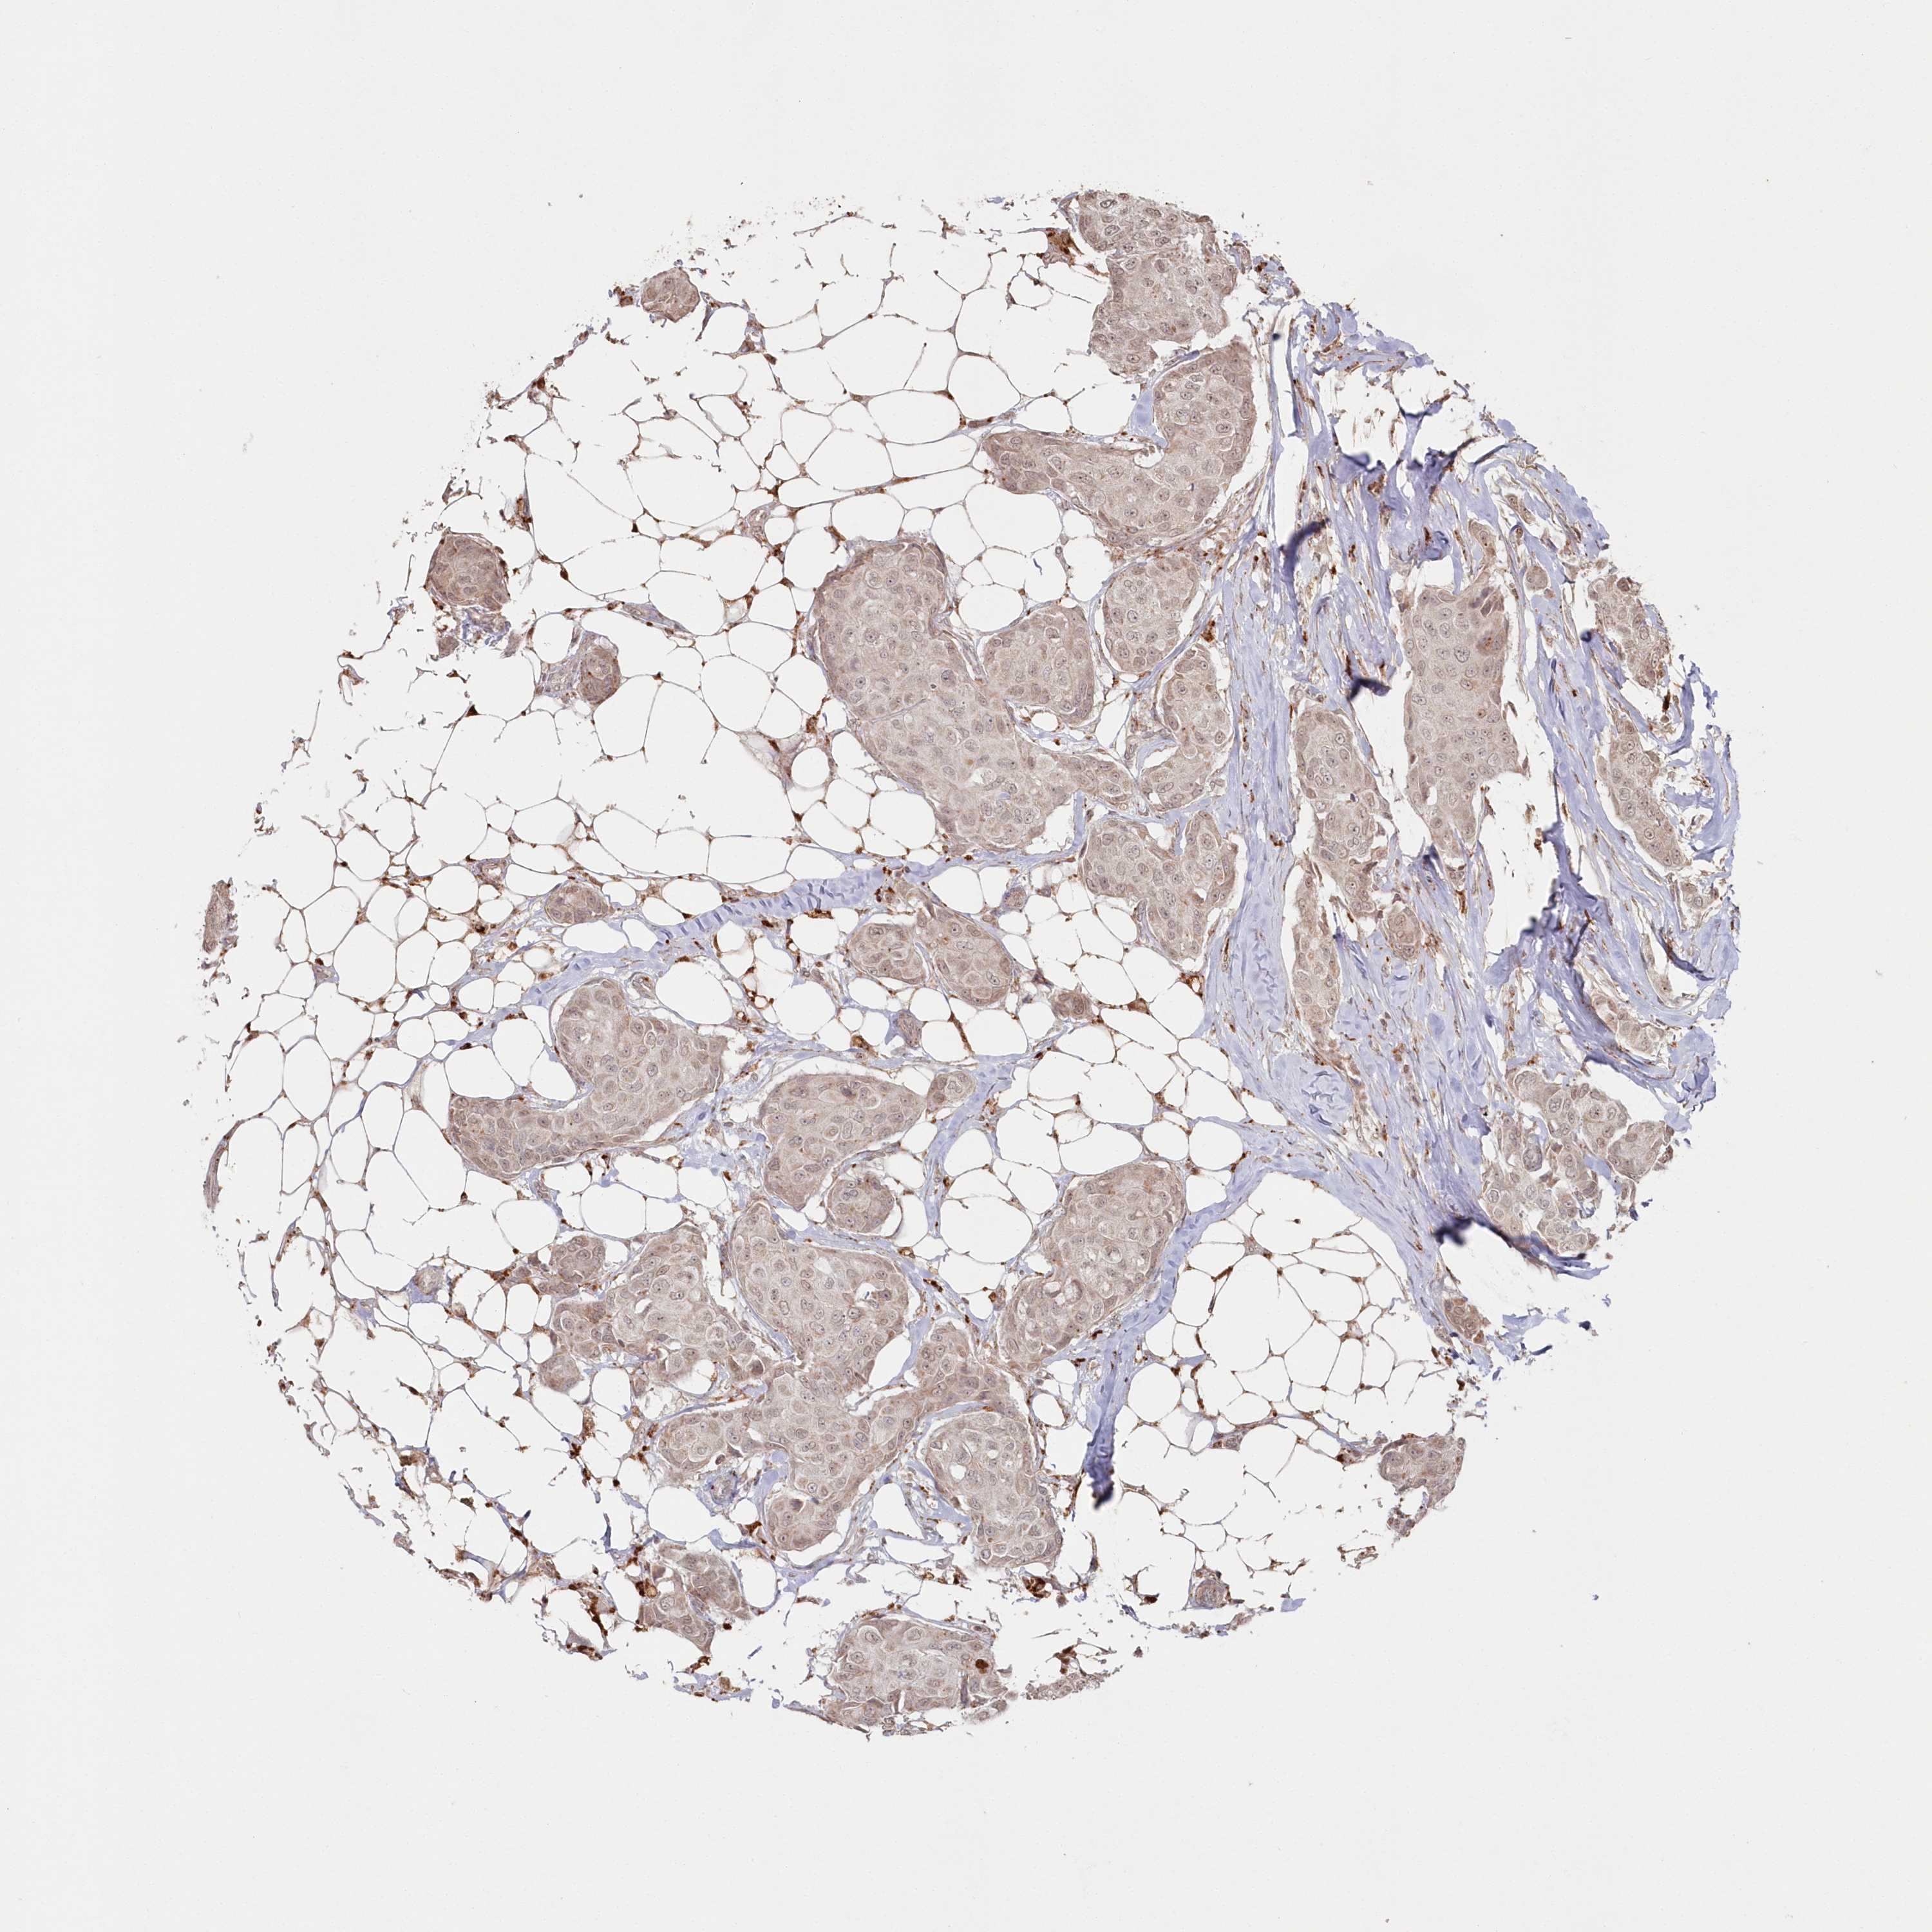

CANCER BREAST CANCER Show tissue menu

BRCA TCGA BRCA VALIDATION PROTEIN EXPRESSION